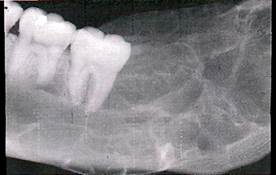

Рентгенологическая картина. Определяется очаг деструкции костной ткани с нечеткими границами. В некоторых случаях может иметь вид мелких ячеистых образований, разделенных костными перегородками.